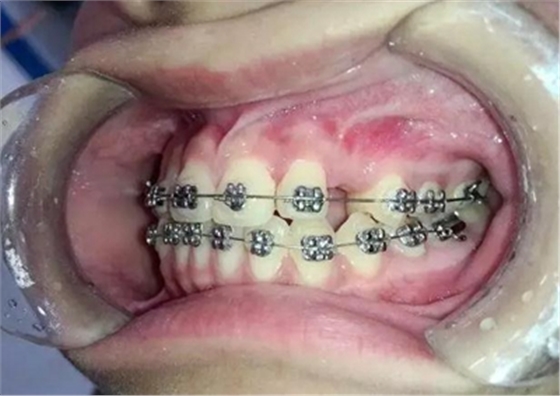

患者13歲,經(jīng)過一段時間的治療前牙反合已經(jīng)正常,只有左上3尖牙埋伏

手術(shù)切開,去除上部牙槽骨暴露出來牙尖,可以看到尖牙緊緊壓在側(cè)切牙根尖唇面上。

粘上舌側(cè)扣用結(jié)扎絲附弓結(jié)扎